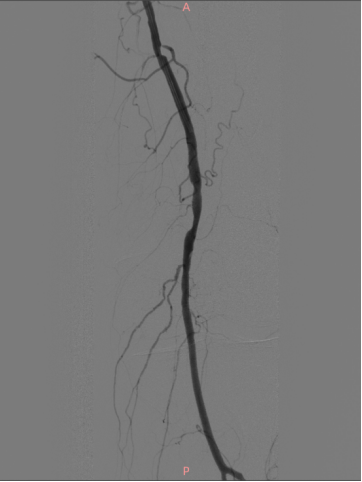

★ 术后造影

病变解除,管腔及血流恢复通畅,未见夹层及造影剂外渗